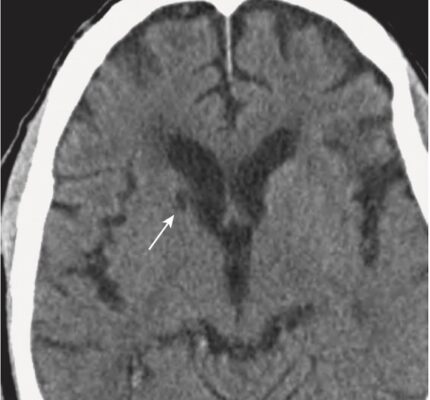

- Sau khoảng 2 tháng, có thể chỉ còn lại một vùng nhỏ giảm đậm độ (Hình 19; Box 1).

- Các dấu hiệu về hình ảnh học cũng tương tự như các dạng não úng thủy thông khác và gồm giãn não thất, đặc biệt là sừng thái dương, với các rãnh não bình thường hoặc dẹt (Hình 25).